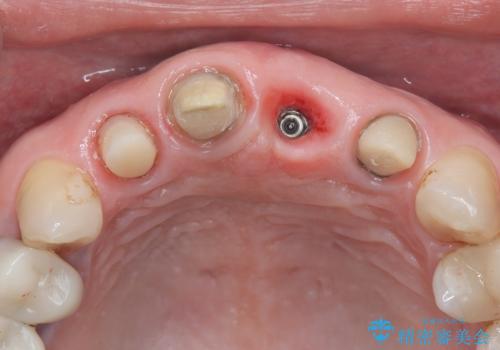

- 治療計画

- 患者様は前歯の審美的な改善を希望されて来院されました。診査の結果、左上1の歯は過去の根管治療により歯根が破折していることが判明し、保存が難しい状態でした。そのため、**長期的な予後を考慮し、抜歯と同時にインプラントを埋入する「抜歯即時インプラント」**を計画。また、隣接する左上2の歯には感染が見られたため、歯根端切除術を同時に行い、感染の除去と治癒を促しました。右上1・2については、セラミッククラウンによる審美修復を行う方針としました。

左上1は抜歯と同時にインプラントを埋入し、骨や歯ぐきの形態を維持しながら治療を進めました。左上2は歯根端切除術により感染部位を除去し、保存治療を実施。右上1・2も含めた前歯4本をセラミッククラウンで修復し、自然な色調と形態を再現しました。治療後は、噛み合わせの安定とともに、美しく自然な前歯を回復することができました。患者様からも「見た目がとても自然で、自信を持って笑えるようになった」と喜びの声をいただきました。